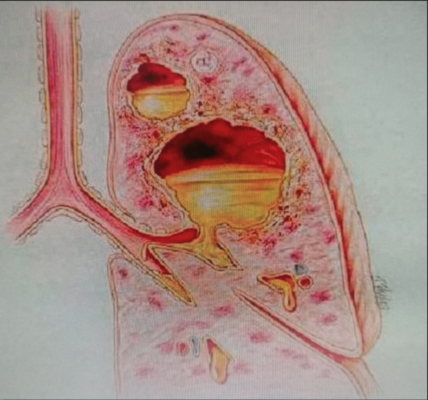

Bệnh Whitmore là bệnh truyền nhiễm có thể lây cho người hoặc động vật. Nguyên nhân gây bệnh là do vi khuẩn Burkholderia pseudomallei tồn tại trong nước và đất bị ô nhiễm. Bệnh này chủ yếu xảy ra ở các nước khí hậu nhiệt đới, đặc biệt là ở Đông Nam Á và miền bắc Australia do lây truyền sang người và động vật thông qua tiếp xúc trực tiếp với nguồn bệnh bị ô nhiễm.Việt Nam là một trong số những vùng lưu hành của bệnh. Bệnh có biểu hiện lâm sàng rất đa dạng, khó chẩn đoán và tỷ lệ tử vong cao ở những trường hợp viêm phổi nặng, nhiễm trùng máu và sốc nhiễm trùng. Bệnh Whitmore có tỷ lệ tử vong từ 40 – 60%, có thể diễn tiến cấp tính hoặc bán cấp tính. Các triệu chứng có thể nhầm lẫn với các bệnh khác và có thể gây ra sự chậm trễ trong việc điều trị kháng sinh thích hợp. Thậm chí, sau khi điều trị thì bệnh nhân vẫn có thể tái phát về sau. Trường hợp nhiễm khuẩn cấp tính có thể tử vong trong vòng 1 tuần kể từ khi phát bệnh. Vi khuẩn có thể làm hoại tử và chết các mô trong cơ thể, ở da thì viêm loét hay áp xe, ở phổi thì gây viêm phổi, trong máu thì gây nhiễm trùng máu…Các trường hợp mạn tính được phát hiện khi có những ổ áp xe phát triển âm thầm ở các vị trí mô hoặc cơ quan khác nhau. Vấn đề phòng ngừa và điều trị đối với bệnh Whitmore cho đến nay là một thách thức lớn. Hiện nay vẫn chưa có vắc xin phòng bệnh. Biện pháp phòng bệnh hiệu quả nhất là sử dụng các thiết bị bảo vệ cá nhân như ủng và găng tay không thấm nước để bảo vệ chống tiếp xúc với đất, nước nhiễm vi khuẩn và làm sạch hoàn toàn vết rách da, trầy xước hoặc bỏng bị nhiễm bẩn

Bệnh nhân nam, 19 tuổi, tiền sử khỏe mạnh. Cách nhập viện 8 ngày biểu hiện mệt mỏi, ho, sốt, đau tức ngực trái. Nhập viện vào khoa Hồi sức cấp cứu, Bệnh viện Quân y 17 trong tình trạng rất nặng với triệu chứng mệt nhiều, sốt cao, khó thở, suy hô hấp. Khoa Hồi sức cấp cứu đã tiến hành cấp cứu kịp thời, thực hiện đặt nội khí quản, thở máy, nội soi khí phế quản để tầm soát tổn thương, lấy mẫu bệnh phẩm cấy khuẩn và làm kháng sinh đồ. Kết quả xét nghiệm máu cho thấy tình trạng nhiễm trùng máu rất nặng. Kháng sinh phổ rộng được sử dụng ngay lập tức theo kinh nghiệm. Kết quả chụp cắt lớp vi tính phổi trái bị xẹp hoàn toàn, có nhiều đám tổn thương đông đặc và tràn dịch màng phổi mức độ nhiều. Ngay khi có kết quả cấy đờm là vi khuẩn Burkholderia pseudomallei và kháng sinh đồ nhạy cảm với một số kháng sinh. Bệnh nhân được điều trị ngay theo kháng sinh đồ và đáp ứng tốt với kháng sinh. Bệnh diễn biến khá hơn, hết sốt, tuy nhiên vẫn còn đau ngực trái nhiều, khó thở. Chụp lại cắt lớp vi tính lồng ngực phổi trái vẫn còn tổn thương nặng. Bệnh viện Quân y 17 đã hội chẩn với Bệnh viện 175, Bệnh viện Đà Nẵng thống nhất phẫu thuật mở ngực bóc vỏ phổi, làm sạch màng phổi, cắt lọc tổ chức phổi hoại tử, dẫn lưu khoang màng phổi, tiếp tục điều trị phối hợp thuốc, đồng thời tăng cường nuôi dưỡng tích cực, cân bằng nước điện giải, khoáng chất, tập phục hồi chức năng hô hấp. Sau 1 tháng điều trị, bệnh nhân phục hồi, toàn trạng ổn định, chuyển khoa khác tiếp tục điều trị duy trì